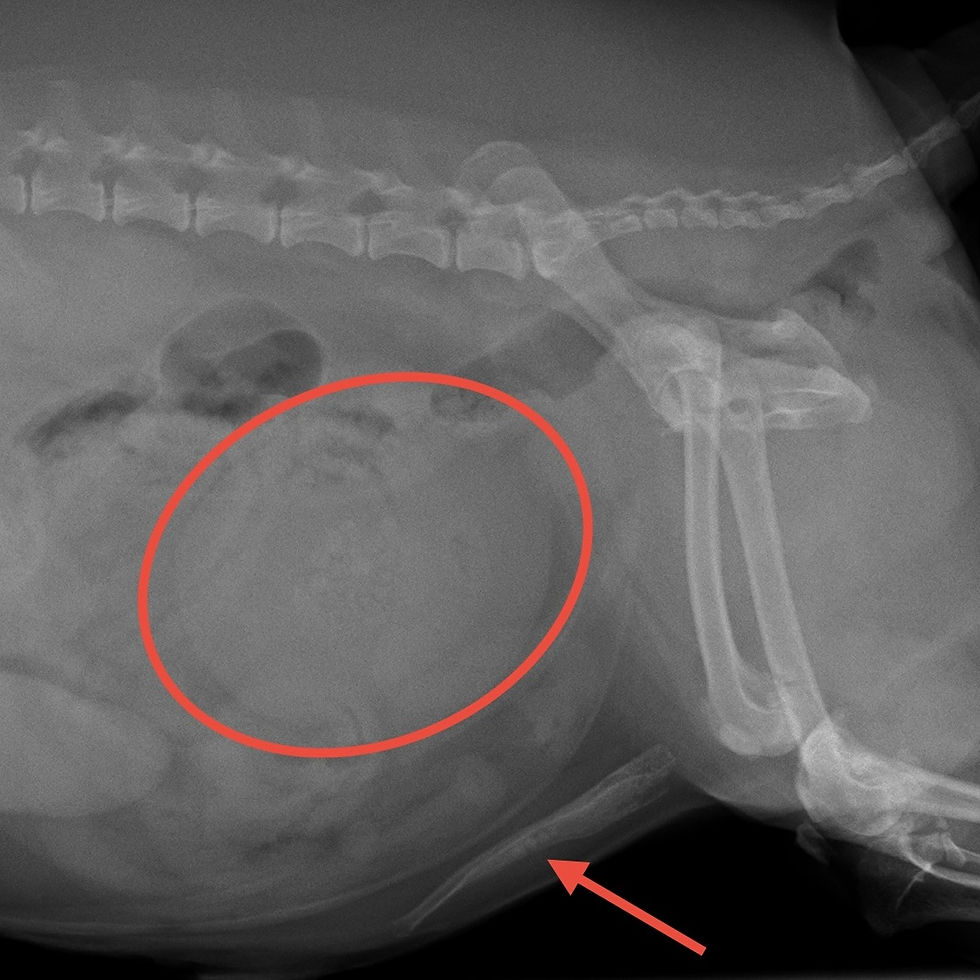

レントゲン検査と超音波検査を確認すると、膀胱内(赤丸)に多数の結石と、尿道内にも結石(矢印)が詰まっていました。

手術前と手術後の画像検査を比較すると、結石がすべて摘出されたのが分かります。